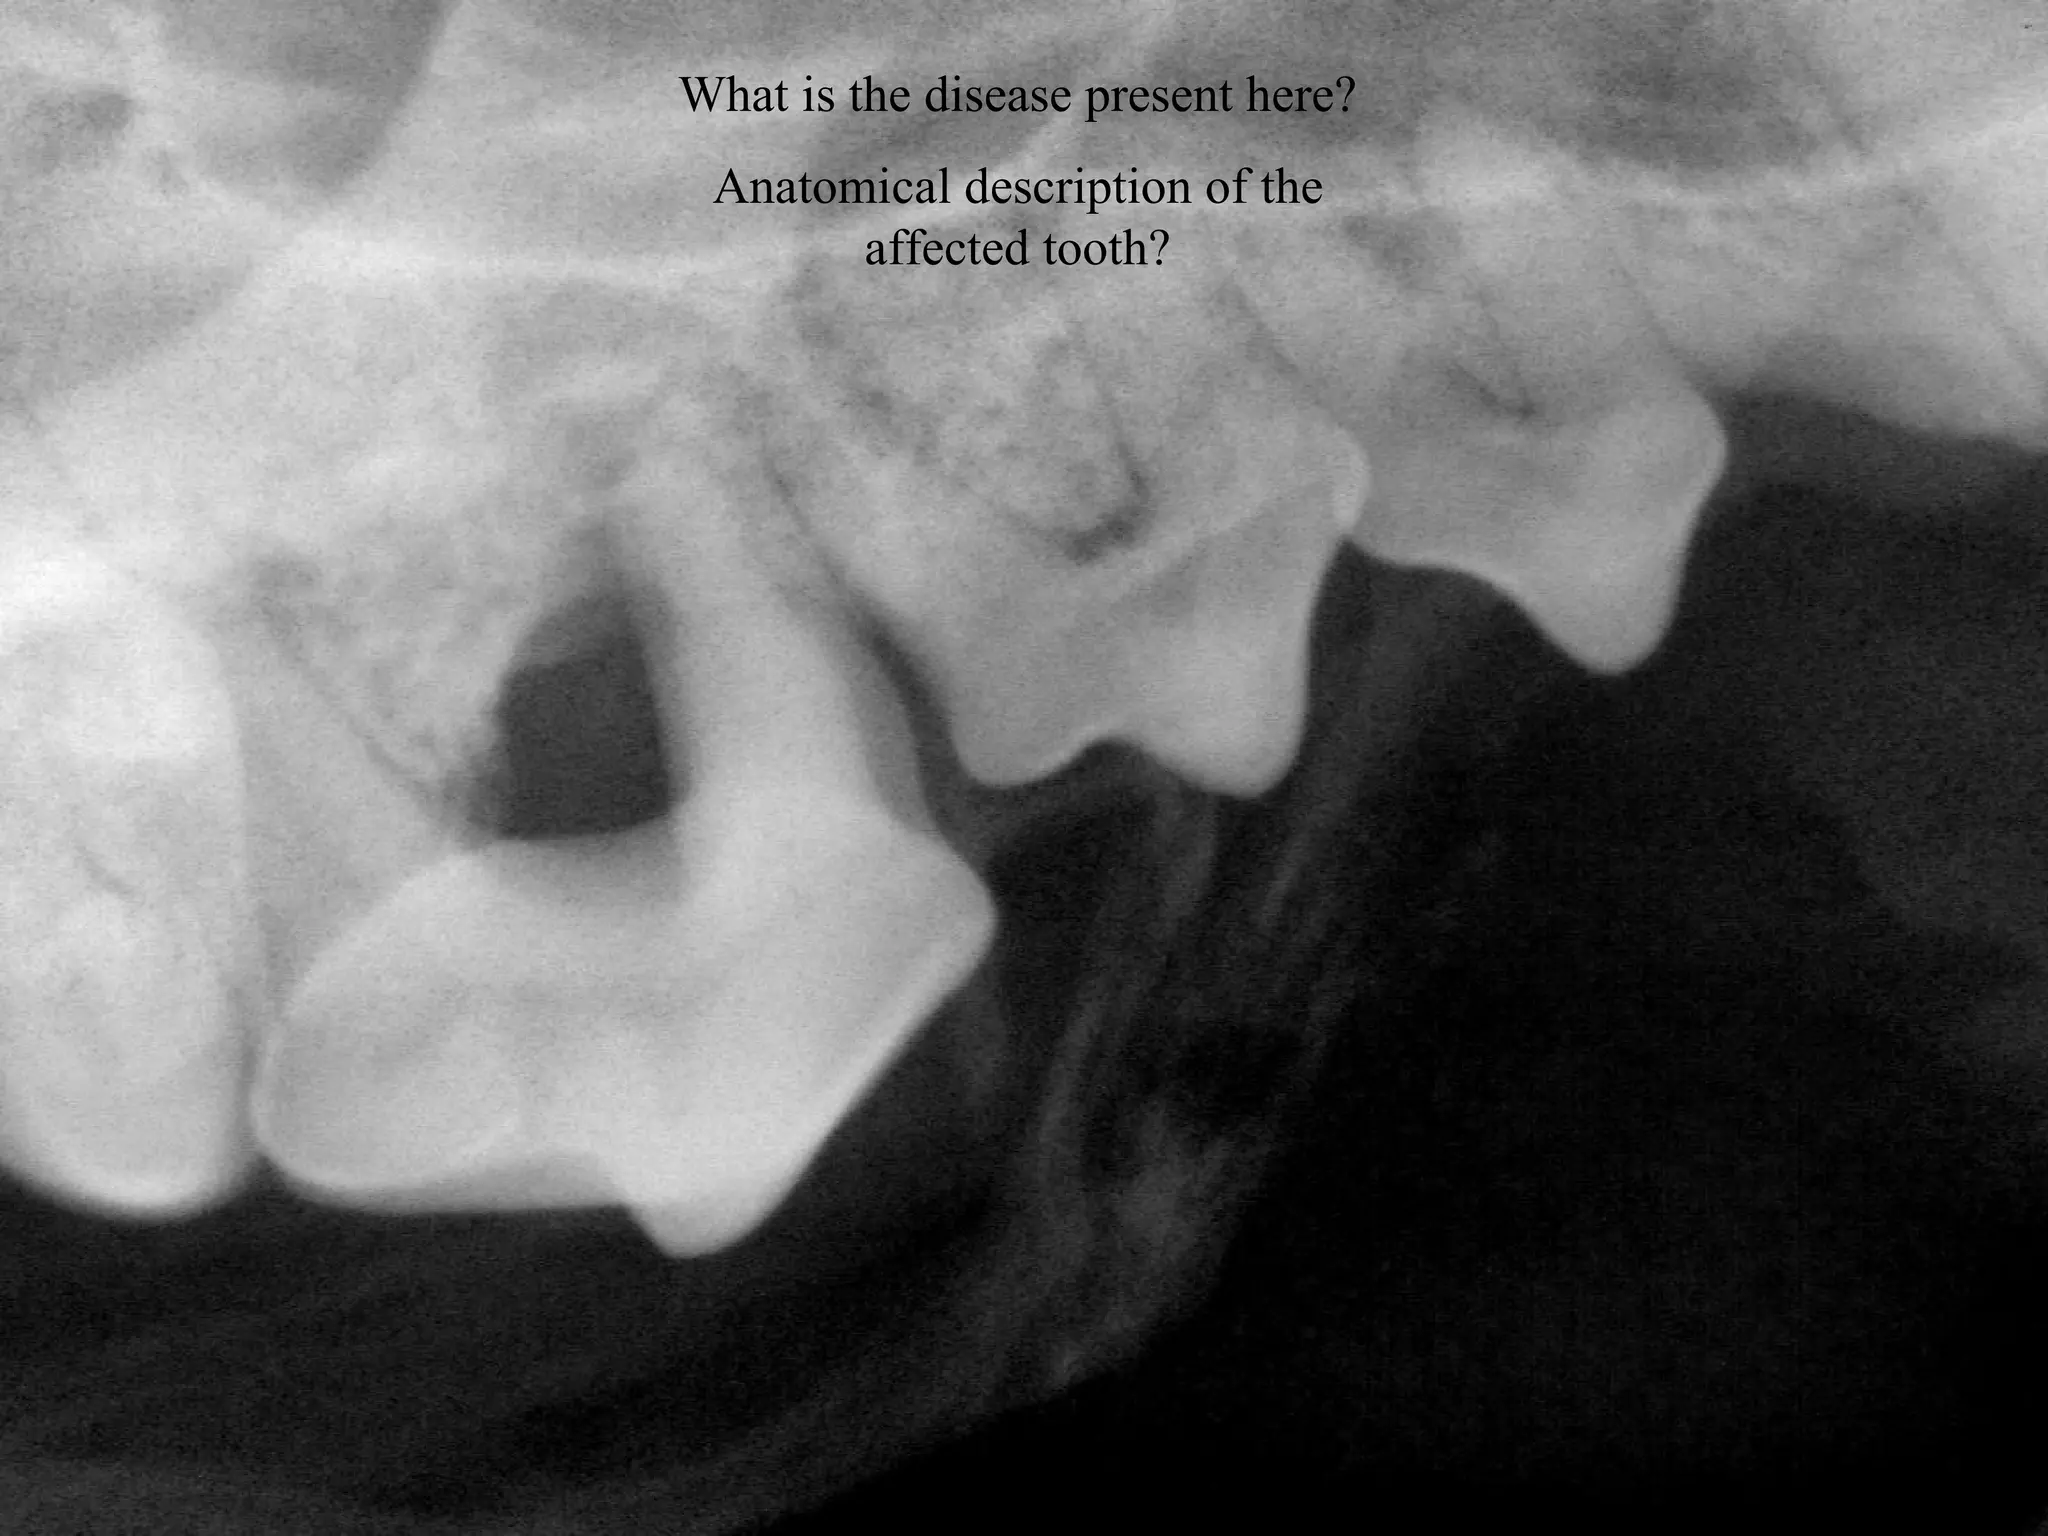

What is the disease present here?

Anatomical description of the

affected tooth?

• 38.

What is thedisease present here? Anatomical description of the affected tooth? 38